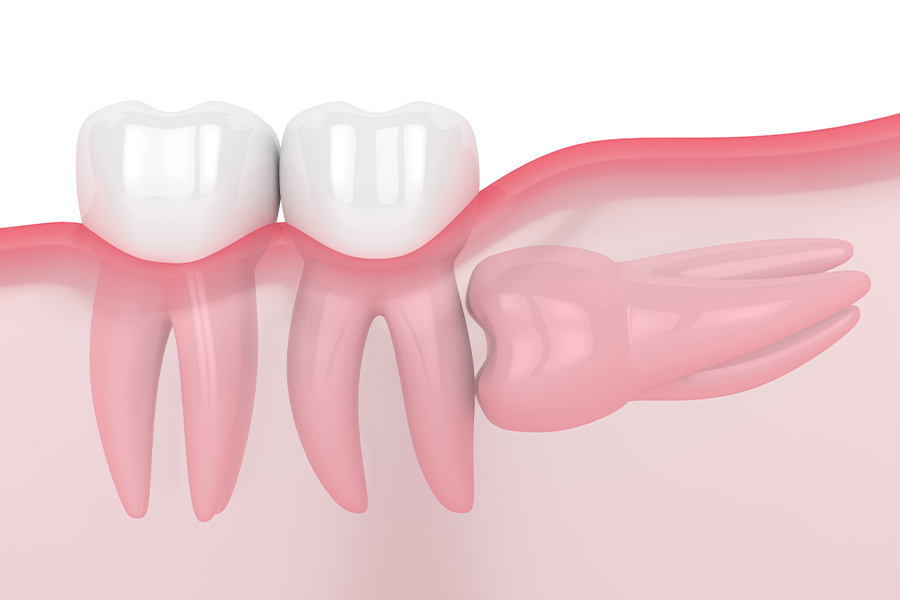

親知らずの生え方

-

水平埋伏のケース

親知らずが横を向いて埋まっていて隣の歯が虫歯になったり、清掃性が悪いために炎症を起こして腫れてしまうリスクが高いため、抜歯をした方が良いケースです。親知らずと神経が近い場合は、安全のためにCT撮影をして位置関係を確認します。

親知らずは抜いた方が良い?

親知らずが生えてくる場所は歯ブラシが届きにくいので、細菌が繁殖しやすく、虫歯になりやすい状態です。また、親知らずが無理に生えてきて隣の歯を圧迫していたり痛みがある場合や、衛生面でトラブルを引き起こす可能性がある場合は、抜歯をした方が良いケースが多くなります。

親知らずが生えてきてもトラブルを起こしていなければ、必ずしも抜歯をする必要はありません。